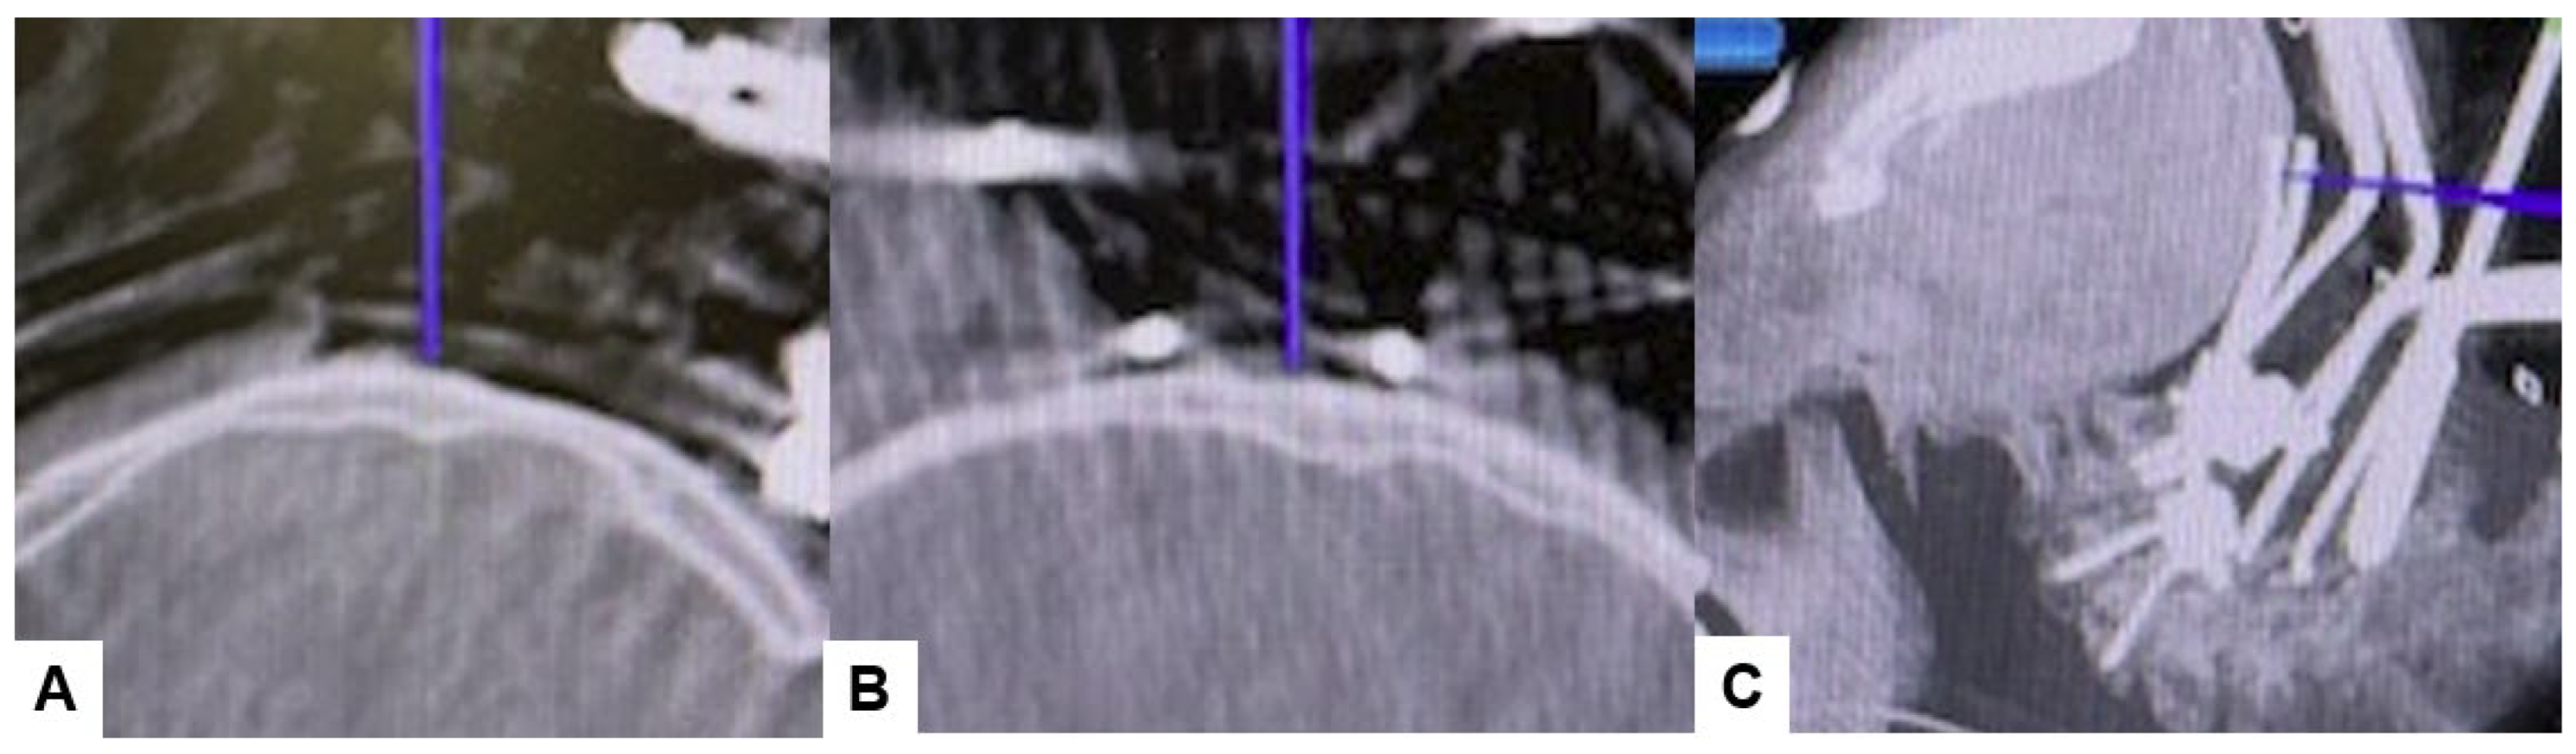

Then, under navigation guidance, the thickest portion for occiput screws was identified, and a total of 6 occipital screws were inserted using a navigated high-speed burr and pointer (Figure 9). The Mayfield skull clamp was loosened and the skull was rotated forward, with traction under neuromonitoring (Figure 10 and Figure 11). Finally, two cobalt–chrome rods were connected to the screw head and more distraction was performed with screw distraction for adequate reduction (Figure 12).

Figure 9.

Occipital screwing, (A) sagittal view, (B) Axial view, (C) 3D view. The adequate screw point is indicated by the navigated pointer.

Positioning occipital screws in occipitocervical instability poses a significant challenge, particularly to precision. It is crucial to accurately identify the thickest part of the lower occiput to safely insert the screws without risking injury to surrounding anatomical structures or the dura, which could lead to cerebrospinal fluid (CSF) leakage (Figure 7). Successful placement of occipital screws necessitates a thorough understanding of bone anatomy and its relationship with neurovascular structures, the spinal canal, hypoglossal canal, vertebral arteries, and the jugular foramen [44]. Using our technique, utilizing a navigation-mapped high-speed burr and probe, we achieved precise insertion of occipital screws with optimal length by directly visualizing and identifying the thickest part of the occiput. This approach, guided by navigation, ensures high accuracy and enhances screw purchase and strength.